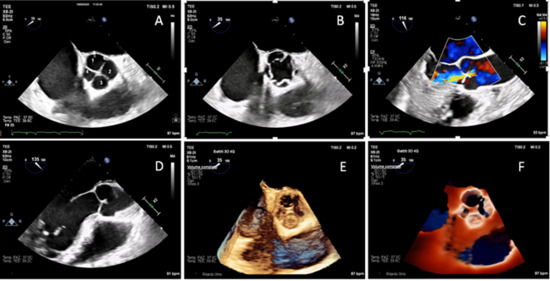

Transoesophageal examination was performed using a X8-2t (Philips, Amsterdam, The Netherlands) probe. Midesophageal aortic valve short-axis view (35° angle) demonstrated four cusps, with two equal-sized larger cusps and two unequal-sized smaller cusps, which means Hurwitz & Roberts type F quadricuspid valve (QAV) (A) [1,2]. Midesophageal aortic valve short-axis view in mid-systole showed the four commissures (B). Color Doppler midesophageal long-axis view demonstrated central moderate aortic regurgitation (vena contracta width = 4 mm, no holodiastolic flow reversal in proximal descending aorta) (C). Midesophageal long-axis view (135° angle) highlighted the characteristic leaflet coaptation pattern of QAV, with a coaptation length of 6 mm measured in end-diastole (D). Three-dimensional high resolution four-beats (61 Hz) standard reconstruction (E) and three-dimensional TrueVue (Philips, NL) rendering (F) provided a detailed visualization of cusps configuration supporting the diagnosis of QAV and its classification (Video S1). QAV is a rare congenital abnormality with a prevalence of less than 0.05% in the general population [3,4]. Hurwitz and Roberts QAV classification is the most widely adopted one, and it identifies seven morphologic variants, from type A to type G [1,2]. This condition is frequently associated with progressive valve dysfunction, primarily due to isolated aortic regurgitation, while significant aortic stenosis is quite rare. The cumulative incidence of aortic valve intervention in QAV is comparable to that observed in bicuspid aortic valve. However, cumulative incidence of aortic surgery in patients with QAV is lower compared to those with bicuspid aortic valve, although it is higher than in the general population [2,5]. Aortic valve replacement with either a mechanical or a biological prosthesis can be performed. However, aortic valve repair should be considered as a first-line option, particularly in young patients with suitable anatomy, even though long-term durability data in this setting remain limited; tricuspidization of a QAV may be an option, particularly in cases with two larger and two smaller leaflets (Hurwitz and Roberts types F and G), or in the case of three larger and one smaller leaflets (Hurwitz and Roberts types B). In the literature, two cases of type F QAV associated with severe aortic regurgitation have been reported, without other significant valvular or aortic lesions. Both patients underwent aortic valve replacement [6,7]. If aortic dilatation is detected, Bentall or Ross procedures should be considered [8,9]. Anatomical studies of normal tricuspid aortic valves reported a mean coaptation length of 3.8 ± 0.8 mm [10]; however, corresponding data on QAVs are currently lacking. QAVs may show a greater coaptation length, potentially related to valve morphology, and future studies on this topic are needed.